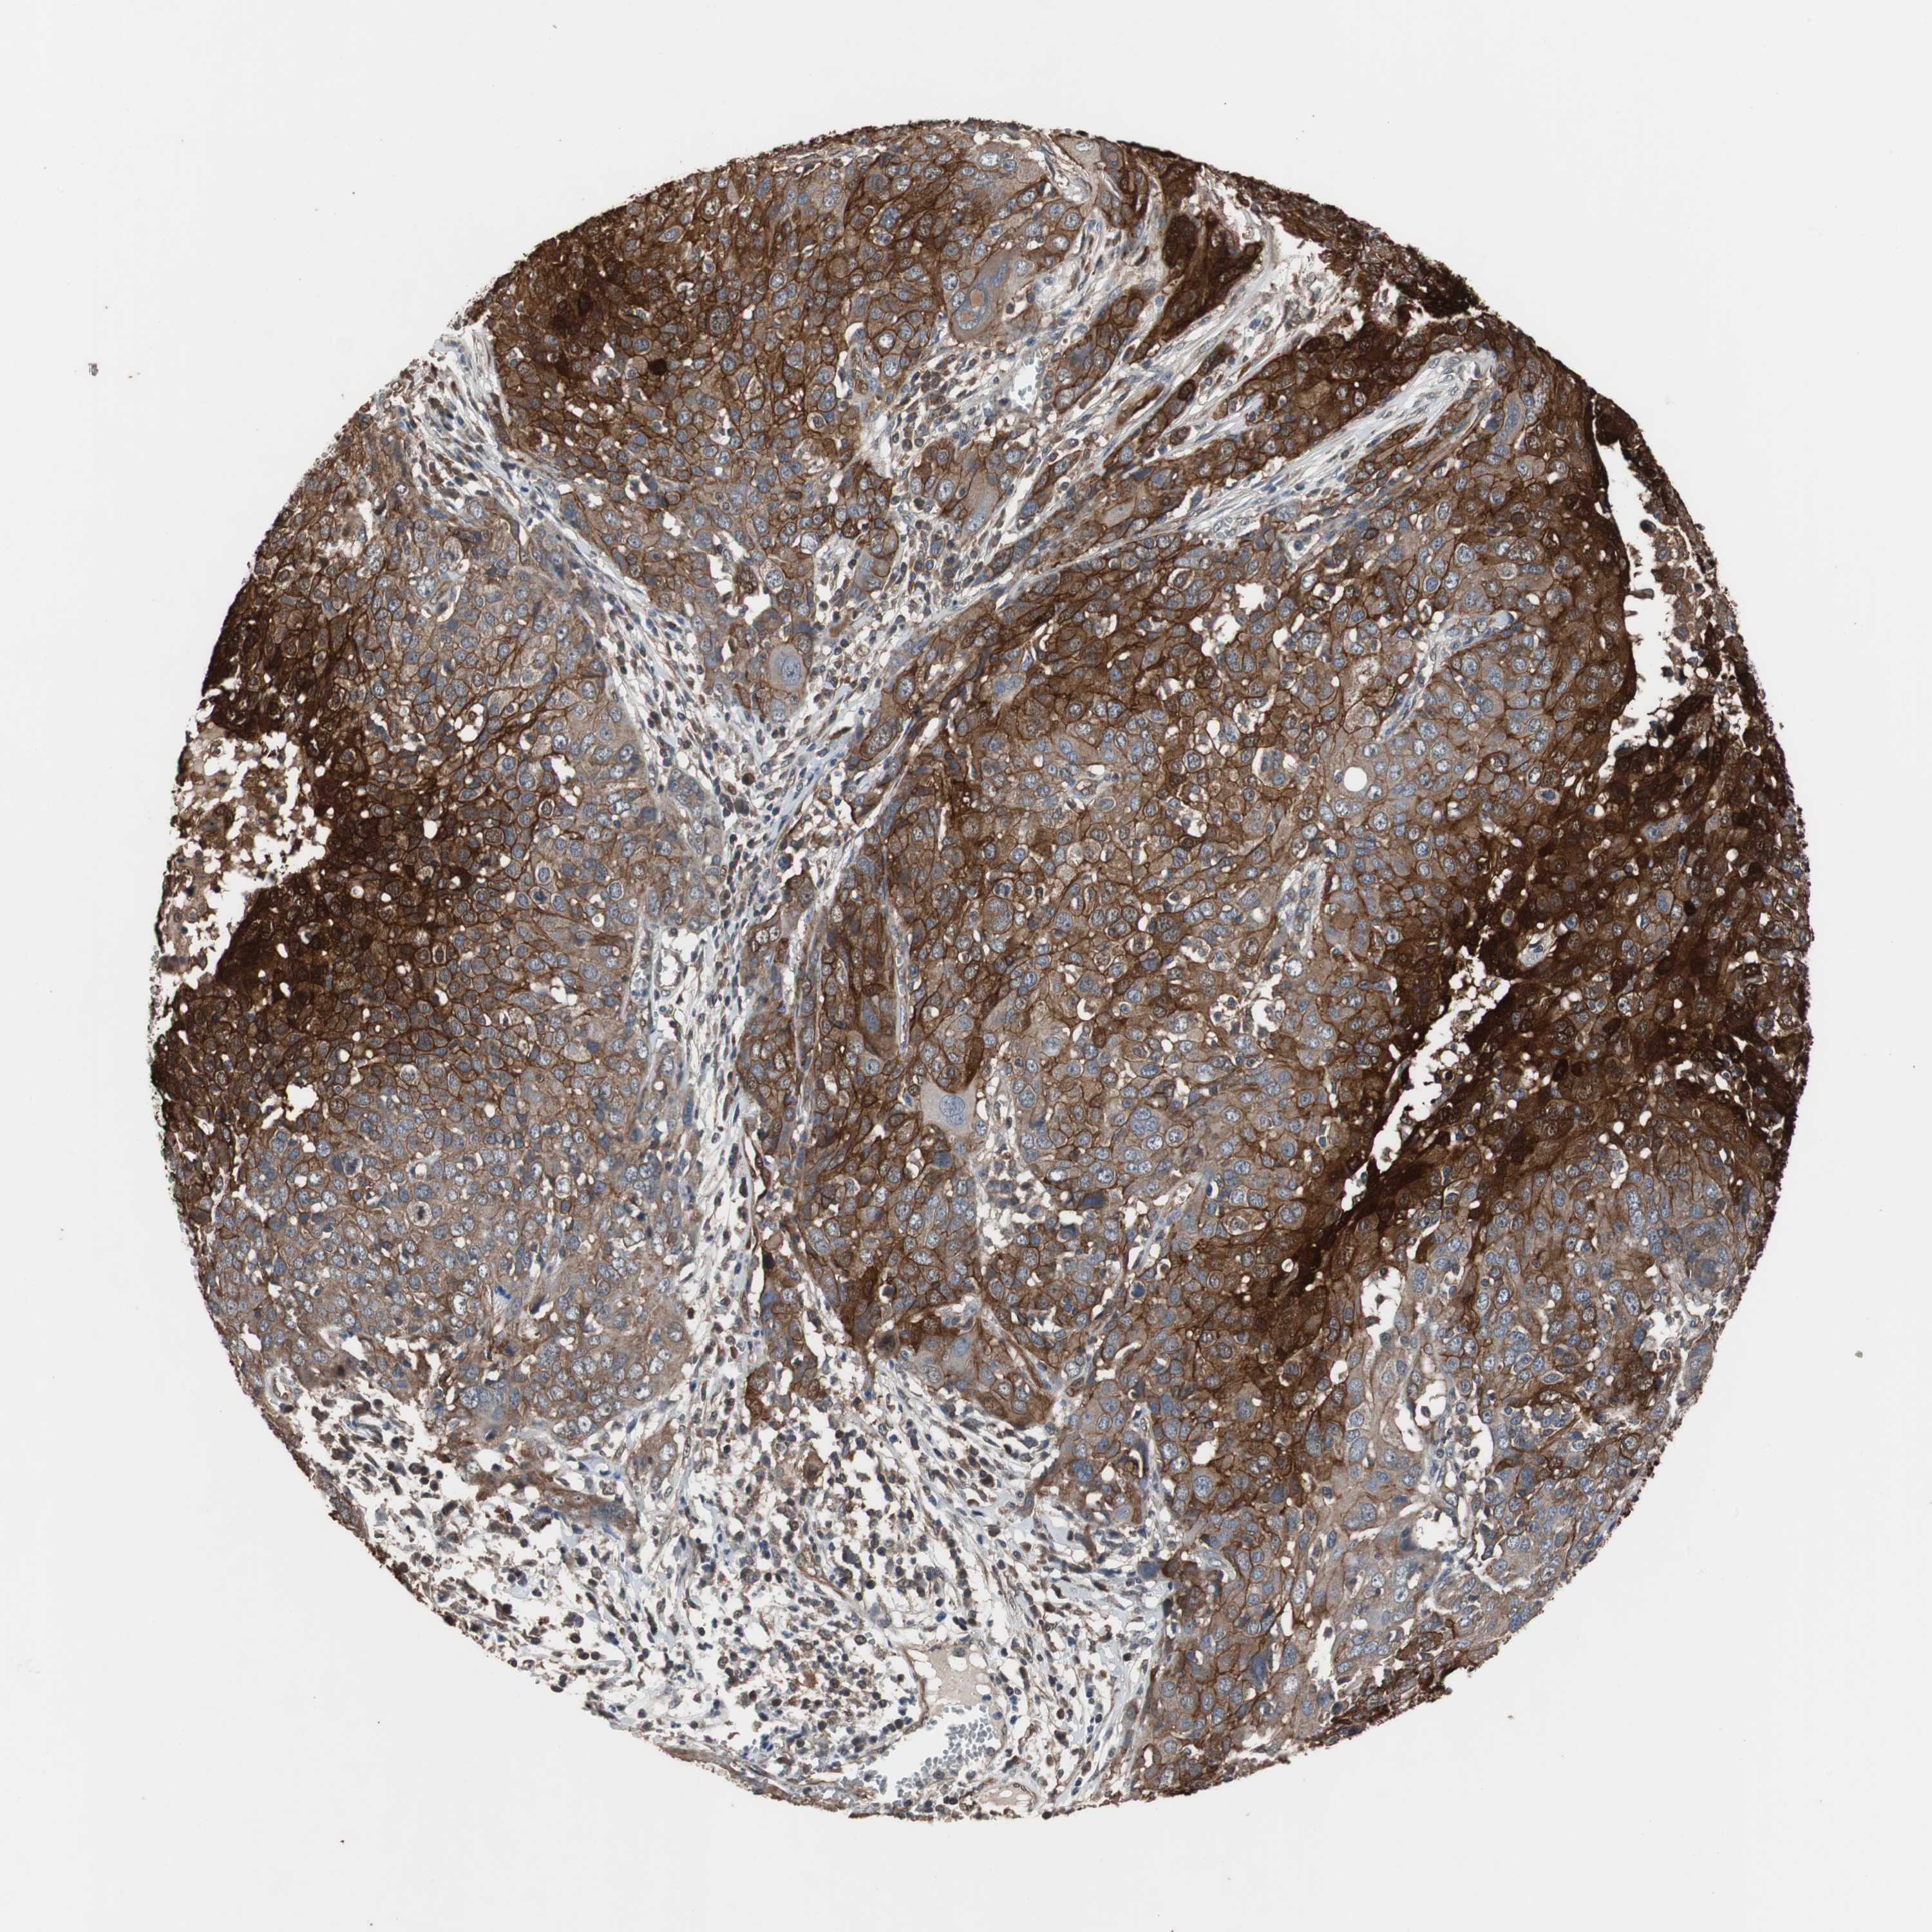

OVARIAN CANCER - Protein expressioni

A mouse-over function shows sample information and annotation data. Click on an image to view it in a full screen mode. Samples can be filtered based on level of antibody staining by selecting one or several of the following categories: high, medium, low and not detected. The assay and annotation is described here.

Note that samples used for immunohistochemistry by the Human Protein Atlas do not correspond to samples in the TCGA dataset.

Antibody stainingi

Antibody staining in the annotated cell types in the current human tissue is reported as not detected, low, medium, or high, based on conventional immunohistochemistry profiling in selected tissues. This score is based on the combination of the staining intensity and fraction of stained cells.

Each image is clickable and will lead to virtual microscopy that enables deeper exploration of all samples and also displays staining intensity scores, fraction scores and subcellular localization as well as patient and tissue information for each sample.

Antibody HPA006881

Staining

High

Medium

Low

Not detected

Intensity

Strong

Moderate

Weak

Negative

Quantity

>75%

75%-25%

<25%

None

Location

Nuclear

Cytoplasmic/membranous

Cytoplasmic/membranous,nuclear

Cystadenocarcinoma, serous, NOS